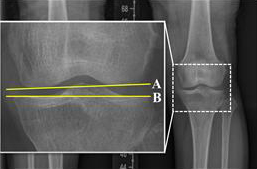

연구팀은 수술 전후 X-ray 사진을 통해 관절선 수렴각(JLCA), 무게중심선 비율(WBLR), 관절선 경사각(Joint Line Obliquity Angle) 등 다양한 방사선학 지표를 분석했다.

분석 결과, 수술 전후 관절선 수렴각(JLCA)의 변화(ΔJLCA)가 1.7°에서 5.6° 사이일 때, 양측 무릎의 퇴행성 관절염 진행이 줄어들고 예후가 개선되는 것으로 나타났다. 또한, 수술 후 JLCA가 1.5°에서 3.9° 사이의 범위에 있을 때, 수술한 무릎과 수술하지 않은 반대쪽 무릎 모두에서 퇴행성 관절염의 진행과 추가 수술의 위험이 가장 낮았다. 반면, 이 범위를 벗어난 경우에는 양 무릎의 예후가 악화될 수 있었다.

특히, JLCA가 과대 교정된 경우(내측 관절선 열림이 큰 상태, ΔJLCA가 5.6°보다 큰 경우)에는 수술하지 않은 반대쪽 무릎에서 관절염이 더 빠르게 진행되고 수술이 필요할 가능성이 높았다(P = .027, P = .006). 반대로, JLCA가 과소 교정된 경우(내측 관절선 열림이 작은 상태, ΔJLCA가 1.7°보다 작은 경우)에는 수술한 무릎에서 관절염이 더 심해지고, 인공관절 치환술로 전환할 가능성이 높았다(P = .014, P = .027).